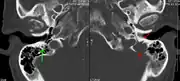

-

X-ray of the forearm, with lytic lesions -

Skull X-ray showing multiple lucencies due to multiple myeloma -

Multiple myeloma in the upper arm -

Pathological fracture of the lumbar spine due to multiple myeloma -

A CT of the brain revealed a lytic lesion in the left temporal bone (right side of image), and petrous temporal bones involving the mastoid segment of the facial nerve canal. Red arrows: lesion; green arrow: normal contralateral facial nerve canal. The lesions are consistent with a myeloma deposit.

CT scan of the lower vertebral column in a man with multiple myeloma, showing multiple osteoblastic lesions: These are more radiodense (brighter in this image) than the surrounding cancellous bone, in contrast to osteolytic lesions, which are less radiodense. -